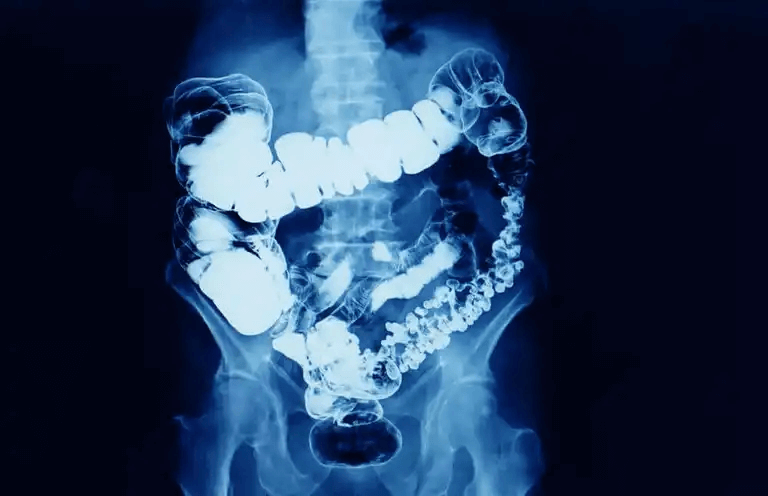

Världsdagen för kolorektalcancer påminner oss om den här cancersjukdomen som är lokaliserad till tjocktarmen och ändtarmen.

Tjocktarmen och ändtarmen är den sista delen av matsmältningskanalen, och kommer efter tunntarmen. Det är här avföringen bildas och kommer att drivas ut från kroppen med avfall från kroppen. Vätska sugs ut från matbolusen i tjocktarmen så att den blir fastare i konsistensen. Avföringen blir sedan lagrad i ändtarmen i väntan på utdrivning.